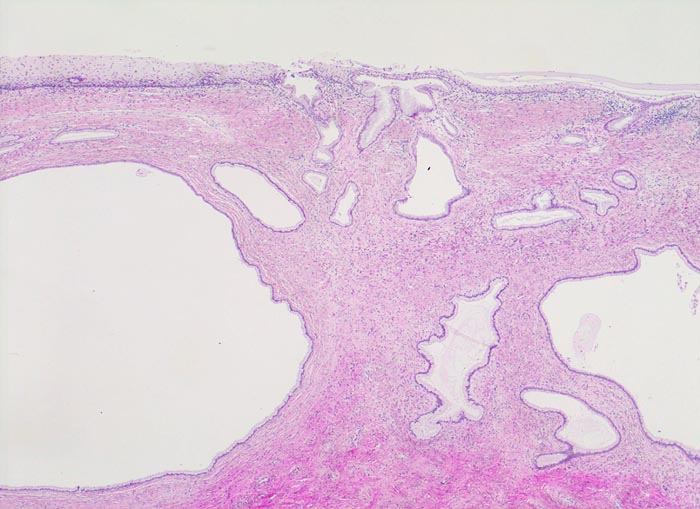

• Portio mit vorderer Muttermundslippe, Anteile der hinteren Muttermundslippe und Zervikalkanal.

• Carcinoma in situ der ektozervikalen Schleimhaut und des metaplastischen Plattenepithels im Bereich der Transitionalzone.

• Einwachsen des Carcinoma in situ in vorbestehende endozervikale Drüsenschläuche.

• Invasive solide Tumorzellstränge in desmoplastischem Stroma mit dichtem lymphoplasmazellulärem Entzündungsinfiltrat.